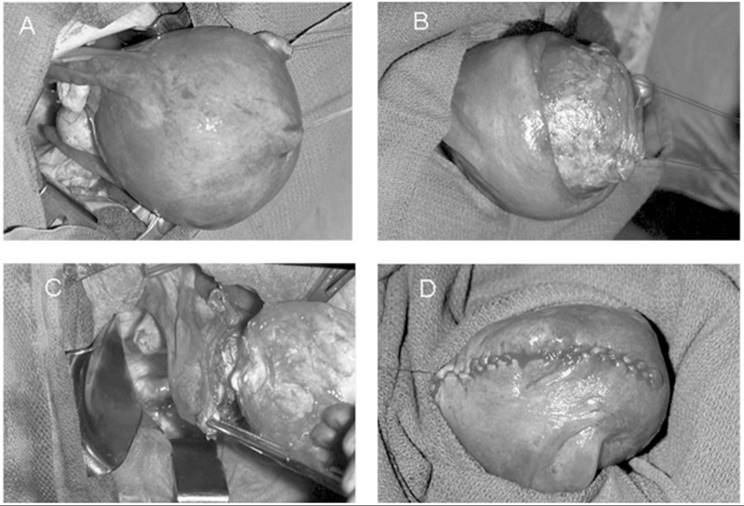

When symptomatic leiomyomata are not completely within the endometrial cavity but in an intramural location, an abdominal surgical approach usually is required. With infrequent exceptions, a low transverse incision yields adequate surgical exposure. Rarely, a vaginal myomectomy can be performed with proper patient selection, but this clinical situation is rare and requires a high degree of surgical skill. The goal of a myomectomy is to remove all the identifiable leiomyomata with the least possible alteration of the reproductive tract. There are numerous surgical techniques but, in general, the myometrium is incised, the myoma dissected from the surrounding myometrium, and the incision closed in layers with absorbable suture to ensure hemostasis and myometrial integrity (Fig. 49.5). Entry into the endometrial cavity is not associated with any significant morbidity, but it is essential not to place sutures though the endometrial cavity wall as if it is a layer to close. Because the distance to the opposite endometrial surface is small, approximating the myometrium underlying the endometrium to the corresponding opposite side is all that is necessary. Cervical fibroids can represent a significant surgical challenge because of their proximity to the bladder and ureters, as well as the difficulty attaining hemostasis. Similarly, parasitic fibroids can be difficult to remove depending on their vascular supply (Fig. 49.6).

FIG. 49.5. Myomectomy. A: Surgical exposure of a large uterus containing an intramural leiomyoma is depicted. The fibroid is dissected from the underlying myometrium in (B). C: The uterine incision is extended down into the cavity and the fibroid is removed. The myometrium is reapproximated in layers (D) and the uterine muscle wall closed.